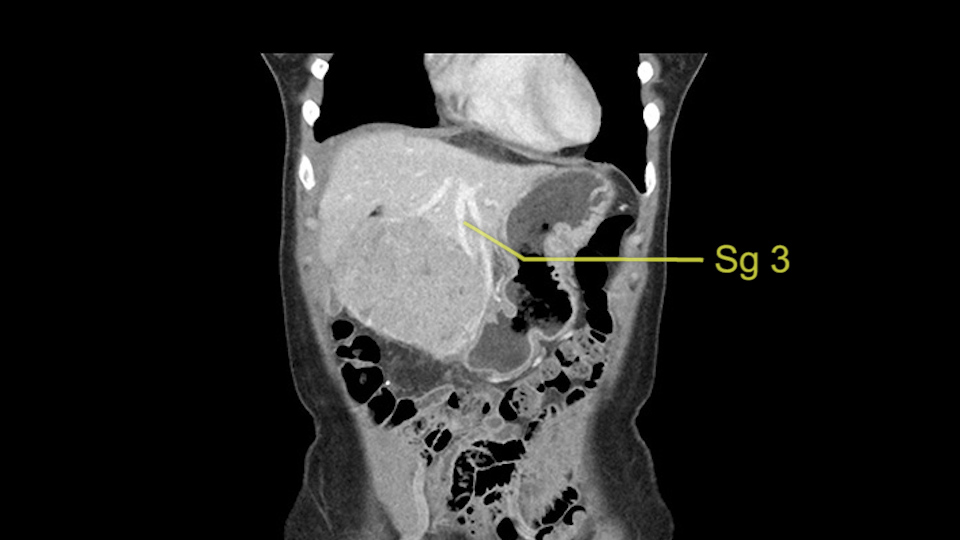

So if we look at the CT scan, on the axial, it’s a larger lesion. It’s about 6 or 7 or 8 centimeters. So it does look a bit threatening in terms of its resectability but if you really drill down deeply into the anatomy, and I think the coronal [imaging] is even better, you can see that the entire mass is on the patient’s left side of the falciform ligament. So it’s really only a left-sided tumor and not even really a left-sided tumor because Segment 4 is uninvolved anatomically.

As I review the CT scan, we have both arterial and venous phases, the tumor is obvious. But I’ll start by saying that the liver itself does not appear to be cirrhotic to my eye. It’s got a normal contour and allied to that, that I do not see evidence of portal hypertension. The spleen is normal, there’s no collateral vessels. The tumor itself, I measured maximally at about 11 centimetres in diameter and I’m told the alpha fetoprotein is very high (over 10000), which is entirely consistent with this being a solitary hepatocellular carcinoma that is very exophytic. It seems to emanate off the inferior margin of Segment 3 (because that’s the falciform). I’ll start by saying that this is not transplantable. The tumor exceeds our guidelines for transplantation, but it's likely resectable based on normal liver and no portal hypertension.

So the issue with regards to resection. A left sided tumor. I believe I can see the falciform ligament right here so we’re looking at a resection of Segments 2, 3 of the left lobe of the liver. The left portal vein is right there. I think we’ll be wiser to take the left portal vein and therefore get well into Segment 4 and do a left hemihepatectomy. Certainly, one does not need to take the middle hepatic vein; it’s miles from the tumor.

Hi my name is Sedat Karademir. I’m from Ankara Guven Hospital and I’m an HPB and transplant surgeon. We are discussing about the case I reviewed the CT of 41 year old lady with a suspected hepatoma in the left lateral segment. Presumably its Segment 3. It looks like a big tumor sitting exophytically mostly out of the liver and pressing on the surrounding organs, but it doesn’t look like any invasion there. In this situation, according to the venous and arterial anatomy, it looks like this will be a Segment 2 and 3 resection.

The other thing I would do in this case is to certainly to assess the coronal phase as we can see in the coronal phase, this tumor looks like it's growing from Segment 3, and again I don’t think there’s involvement of the right side of the liver or even on Segment 4.